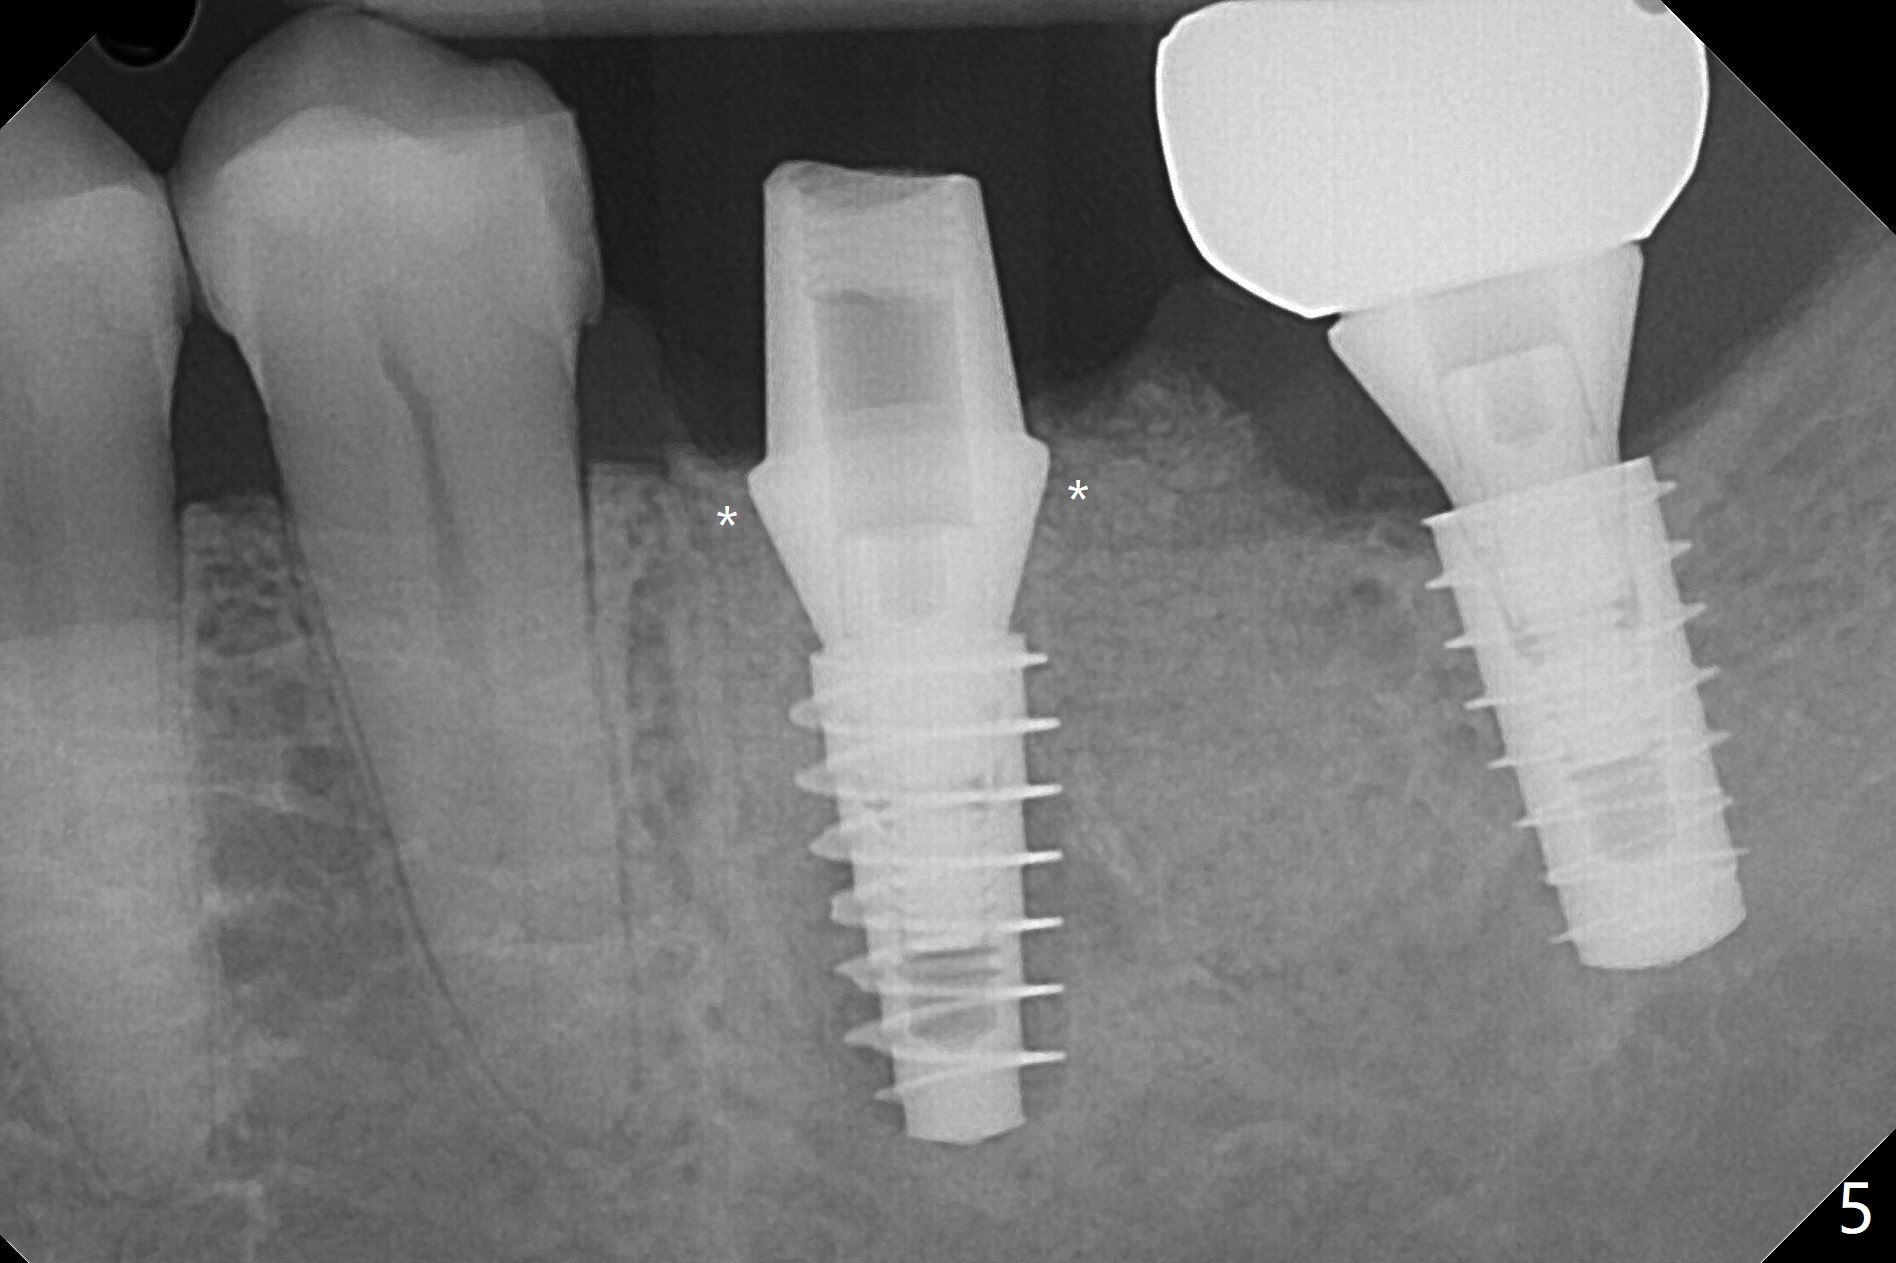

Venopuncture is conducted (Fig.1) for PRF and sticky bone (cortical chip and .5 cc ß-TCP). After use of proximators at #19, cowhorn forceps are applied, resulting in metal crown dislodgement. Since there is distal bone loss, distal socket sheath is contemplated. The tooth is sectioned. When an elevator is inserted between the roots, the distal root is loosened first. The 2 roots are removed, revealing a rounded end septum (Fig.2 S) and a larger distal socket. To avoid osteotomy deviation over the septum, a 12 mm bone trimmer is used, followed by point drill (Fig.3 *). But the lower half of the implant is deviated mesial (Fig.4) with decreased torque (~ 10 Ncm). To overcome this misfortune, the roots should not be removed until osteotomy is finished. Dual zones of bone graft is conducted. Sticky bone is placed until the plateau of the implant with a healing screw in place (Fig.4 * (bone zone)). After placement of a pair abutment, the same bone graft is packed until the margin of the abutment (Fig.5 * (soft tissue zone)). An immediate provisional is fabricated to close the socket with a piece of PRF as well. Fig.6-11 explains why the lower half of the implant deviates to the mesial socket, while Fig.12-16 illustrates how to prevent the deviation. After extraction of #19 (Fig.6,7), the crest of the septum is flattened (Fig.8 arrowhead) to prevent the initial deviation (Fig.9 red line). When a drill reaches a space (a socket, mesial in this case), the drill is deflected to the least resistant area (Fig.10 a bent red line), leading to the implant deviation apically (Fig.11 green). To prevent the apical deviation, therefore, the roots of the affected tooth is temporarily not removed (Fig.12). The osteotomy should not deviates with surgical guide because of similar density between the tooth and the bone (Fig.13). When the osteotomy is finished (Fig.14), the roots are extracted (Fig.15). The implant to be placed should not have deviation (Fig.16 green). The papillae are maintained by the immediate provisional 11 days postop (Fig.17). The incompletely seated abutment at #18 (Fig.5 <) is reseated completely 6 months postop (Fig.18). Crestal bone forms distal to #19 implant. There is no bone loss 4 months and 3 years 1 month post cementation at #19 and 18, respectively (Fig.19,20).